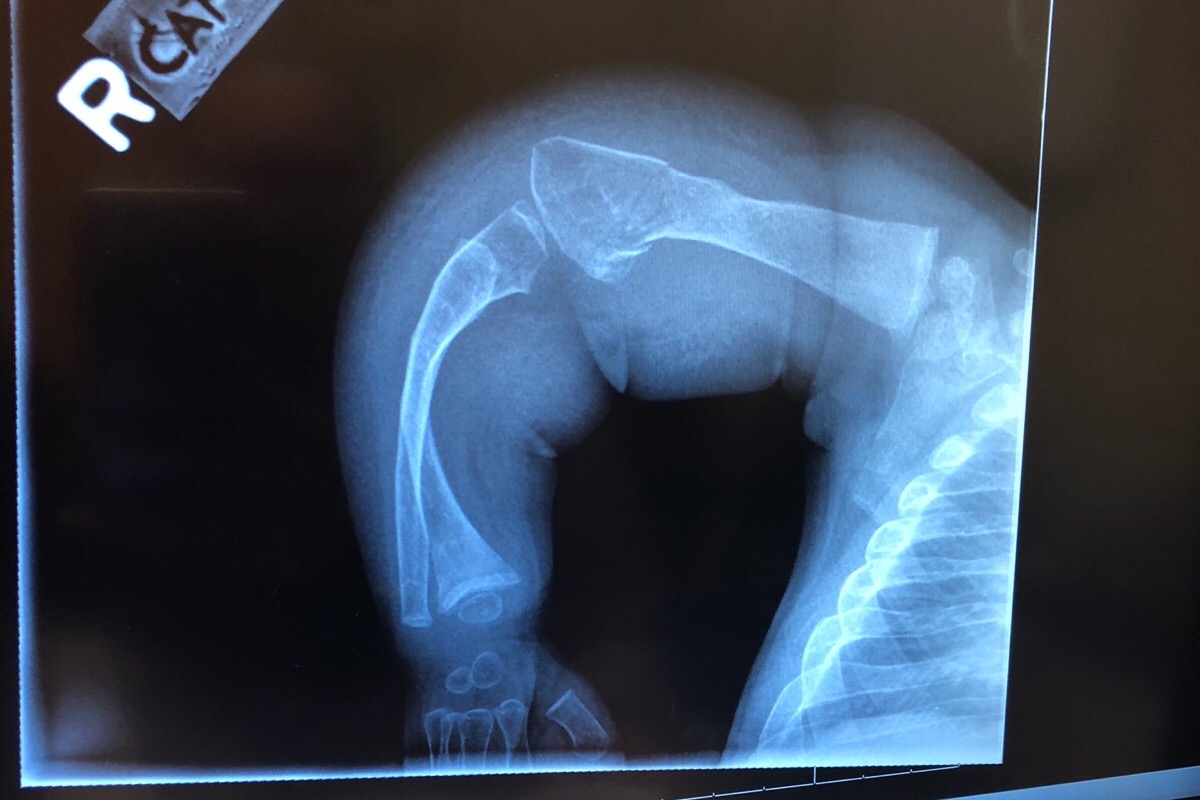

My name is Paola and im Juliet’s mom. Juliet was born September 20,2016. During my pregnancy Juliet’s bones were measuring shorter and they were bowed. The day she was born they immediately rushed her to the NICU due to her not breathing. Later on that day a NICU nurse came to talk to my husband and I and let us know that Juliet had 67 broken bones and they were all in different healing stages and they did not have a reason as to why but if they knew something they would let us know. My husband and I weren’t allowed to hold Juliet until she was about a week old due to her broken bones and not wanting us to cause more. After Juliet being in the NICU for 3 weeks they asked us if we knew what Osteogenesis Imperfecta was and I didn’t even know how to say it so at that point the Dr. told us that she suspected that, that was Juliet’s condition. She contacted a Dr. that specializes in OI and a week later they diagnosed her with type 2 and they let us know that she had already made it 3 weeks and that we don’t know how much longer she was going to live so it was best to take her home to pass away. After 7 weeks we received her genetics report and it turns out she has OI type 8. It’s a really rare type that was just discovered not too long ago. As of today we go along with what Juliet’s body tells us. She will be 3 this year and she has had over 200 fractures in her body. The dr recently decided that Juliet is ready for rodding surgery. First we will start with femurs then we will do Tibias. Hopefully one day Juliet will walk. As you all know anything that involves drs is a lot of money and as much and Juliet’s dad and i want to cover all the expenses it is impossible. The money raised will go towards Juliet’s surgery and wheelchair. We would really appreciate the help and thank you so much ❤️